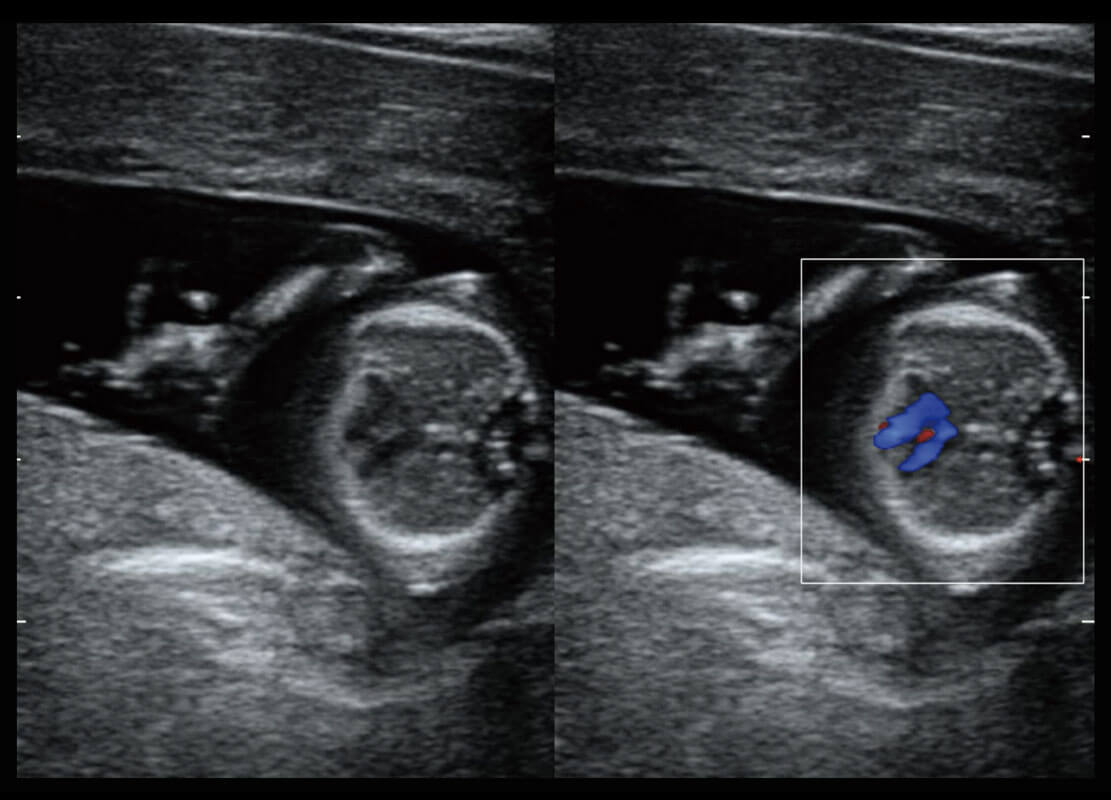

四腔切面

四腔心血流

右室双出口

胎心容积成像